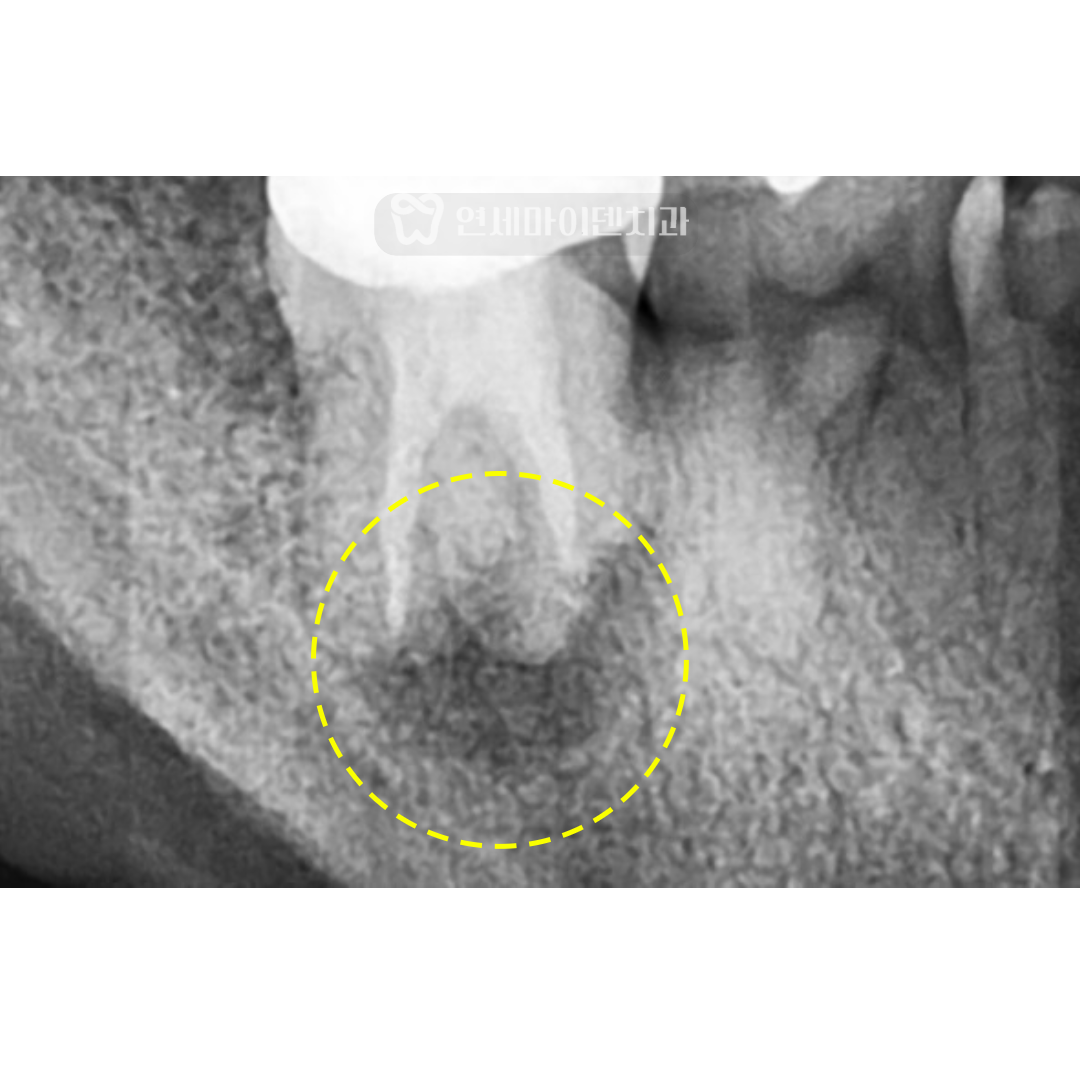

환자분의 치아 엑스레이를 보면

치아 뿌리쪽에 까맣게 보이는 부분이 있습니다.

염증이 생기고 잇몸뼈가 녹으면 이렇게 엑스레이 상으로 까맣게 보입니다.

이 환자분의 경우에도 염증의 양상이 J자 형태를 보여서

살리기 어렵다고 판단할 수도 있었습니다.

하지만, 치료 전 까맣게 녹았던 뿌리가

재신경치료 후 하얗게 차오르는 것이 보입니다.

치료 1년 후 하얗게 뼈가 차오르기 시작했고

2년 뒤에는 완전히 뼈가 회복되었습니다.